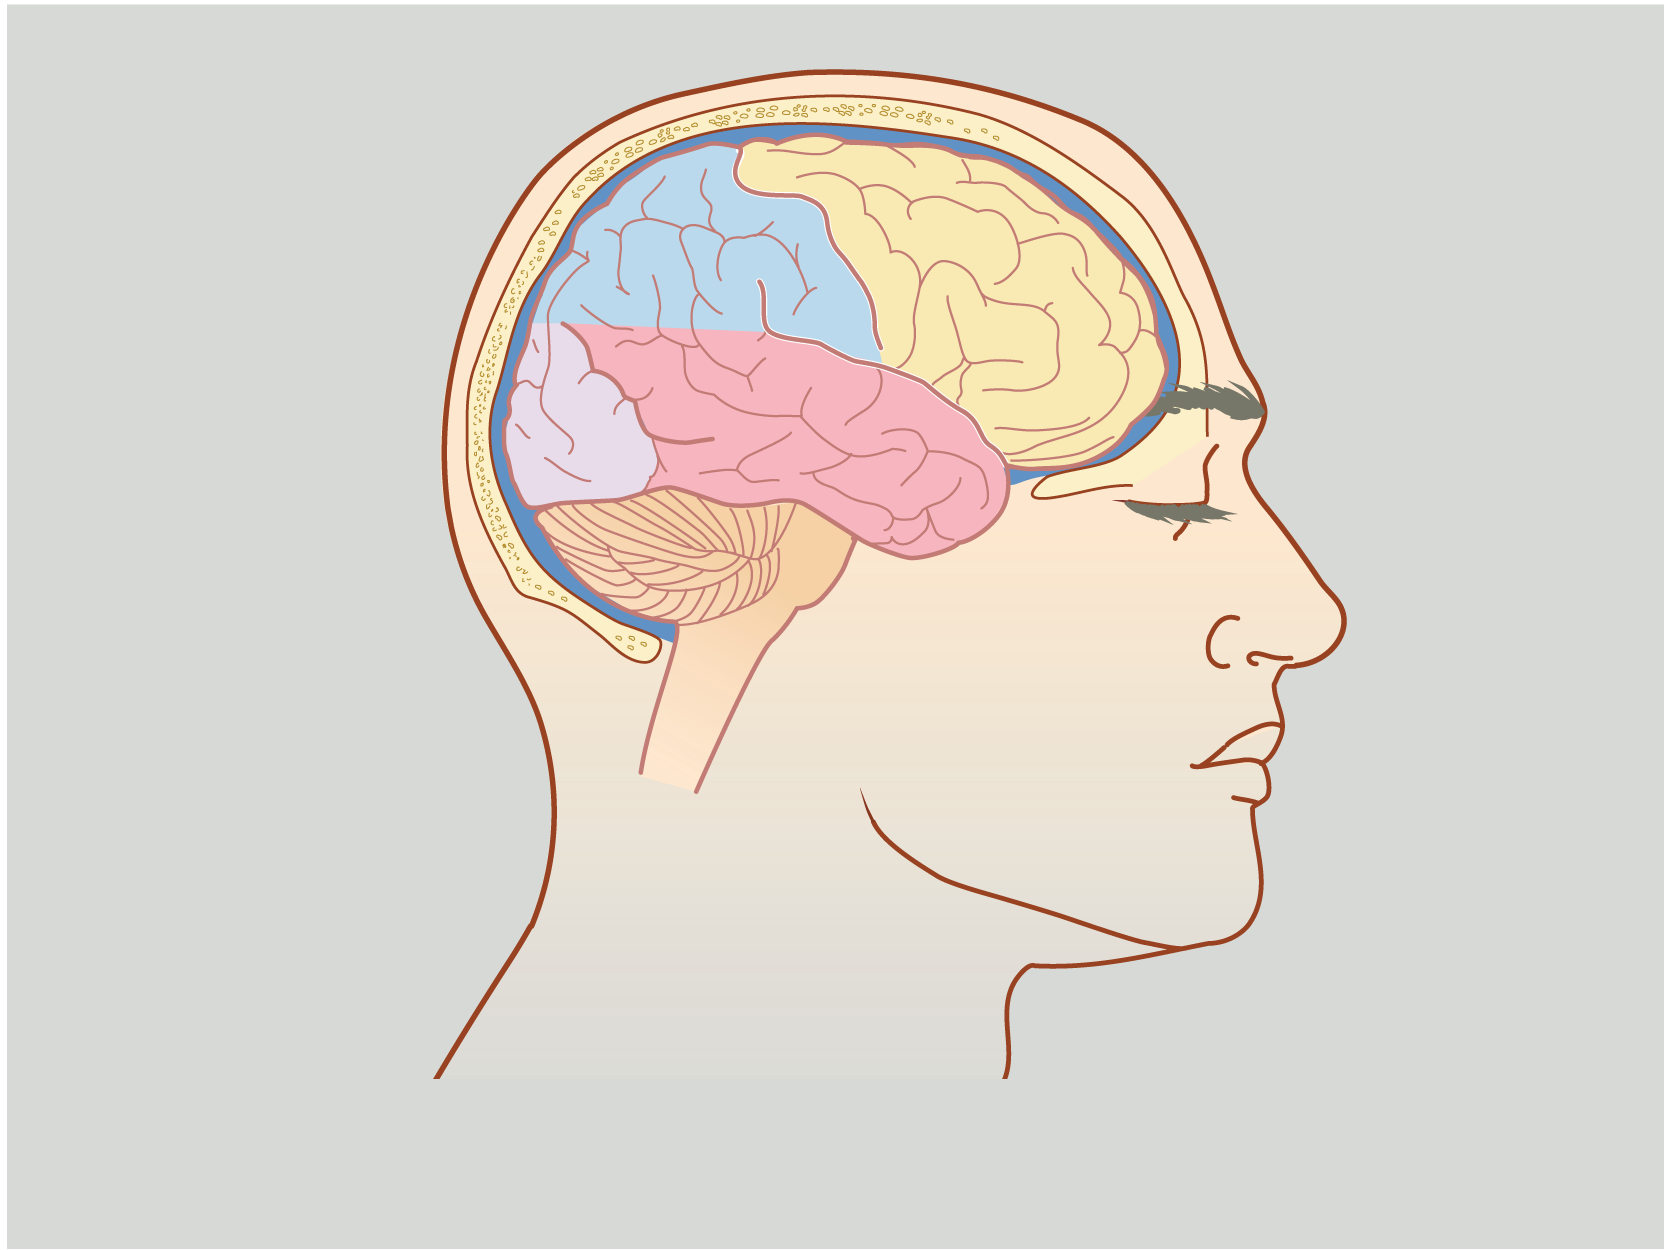

Surgical illustrations visually depict operative techniques, surgical anatomy, and complex procedures. They are created with high anatomical accuracy and serve as a visual bridge between complex surgical knowledge and learners, clinicians, or patients.